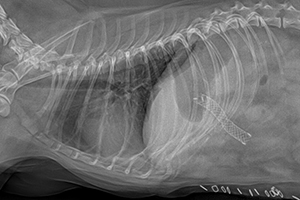

심장사상충 제거술 (Heartworm Removal) 중증 케이스

심장사상충 제거술은 중증 심장사상충 감염으로 인해 약물 치료만으로는 위험하거나 효과가 제한적인 경우 시행되는 중재적 시술입니다. 혈관 카테터를 이용해 심장 또는 폐동맥 내에 존재하는 사상충을 직접 제거함으로써 폐혈관 폐색과 급성 쇼크 위험을 줄이고, 심장 부담을 빠르게 완화하는 데 목적이 있습니다.

심장사상충 제거술

심장사상충 제거술 이미지 1

심장사상충 제거술 이미지 2

안내

환자의 상태와 심장·폐동맥 내 기생충의 위치에 따라 시술 난이도와 접근 방법이 달라질 수 있으며, 시술 전 정밀 영상 평가와 시술 후 모니터링이 필요합니다.